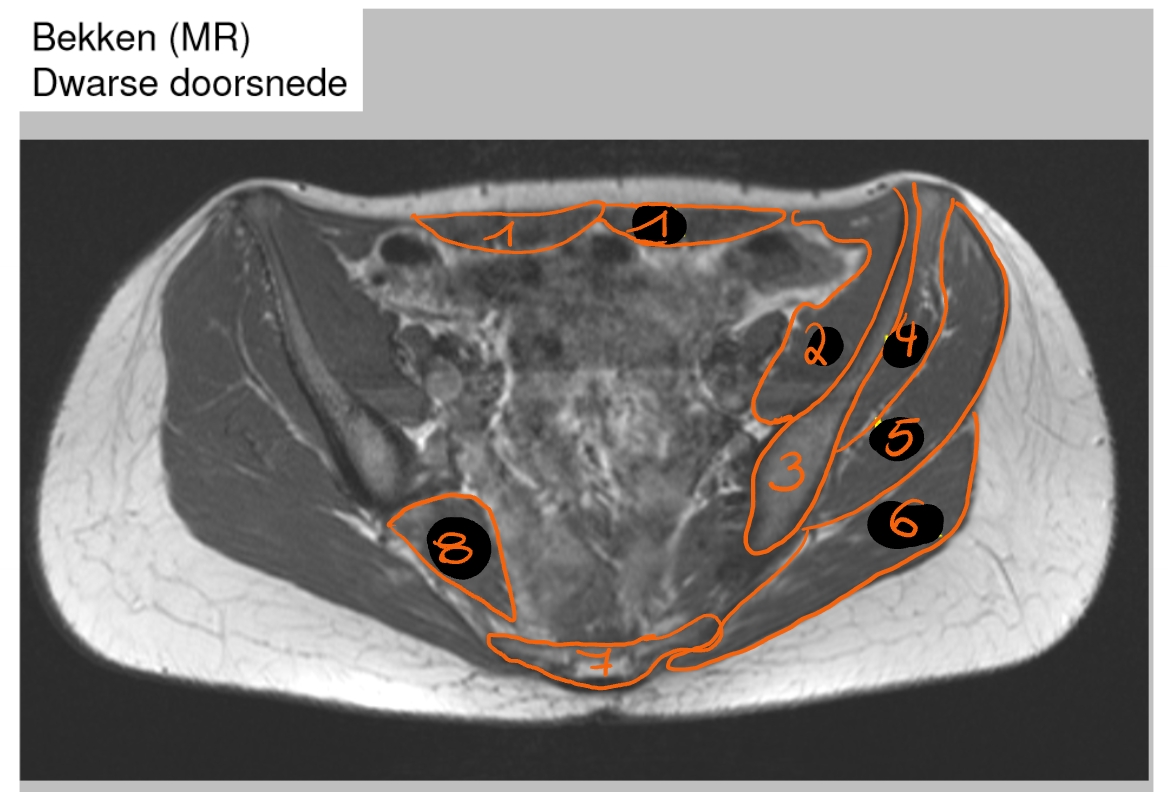

m. rectus abdominis

m. iliacus

os ilium

m. gluteus minimus

m. gluteus medius

m. gluteus maximus

sacrum

m. piriformis

→ MRI bekken: dware doorsnede